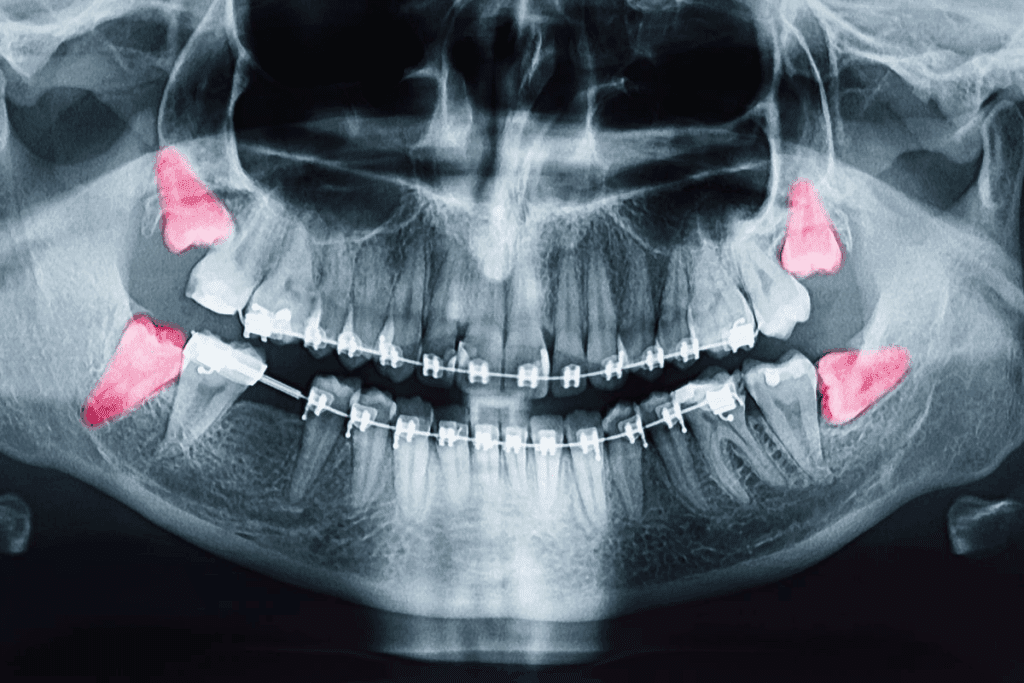

Imaging Tests

Next, we use imaging tests to see more about the tumor. These tests include:

- X-rays: To see the jaw bones and find any problems.

- CT (Computed Tomography) scans: Give detailed images of the jaw and tissues around it.

- MRI (Magnetic Resonance Imaging): Show detailed images of soft tissues and the tumor’s size.

- PET (Positron Emission Tomography) scans: Check the tumor’s activity and if it has spread.

These tests help us understand the cancer’s stage and plan treatment.